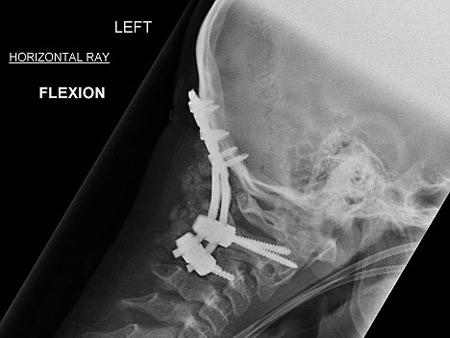

قام الاطباء بتثبيت رقبته إلى جسده بالمسامير |

وعقب حصول الحادث في أواخر العام 2006، قام الأطباء بإخضاع الصبي المصاب إلى عملية جراحية عاجلة استمرت لمدة 7 ساعات، وهي العملية التي نجحوا خلالها في إعادة تثبيت فقرات رقبته وتوصيلها إلى قاعدة الجمجمة باستخدام مسامير وشرائح مصنوعة من معدن التيتانيوم.